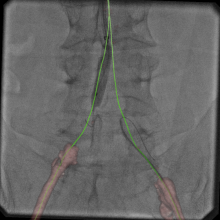

In Part 2 of this 3-part video series on recent advancements in diagnostic radiology, current editorial advisory board member Robert L. Bard, MD, PC, DABR, FASLMS, talks with ITN on the advantages of using power Doppler Sonography as a non-invasive way to screen for prostate tumors with abnormal blood vessels.

Dr. Bard is internationally known and recognized as a leader in his field. He specializes in advanced 3-D Doppler imaging to detect cancers in numerous organs, including the breast, prostate, and other areas. His images are used to accurately guide biopsies, target therapy and provide focused follow-up after treatment. He is committed to improving non-invasive cancer testing and developing minimally invasive image guided technologies to prevent cancer spread.